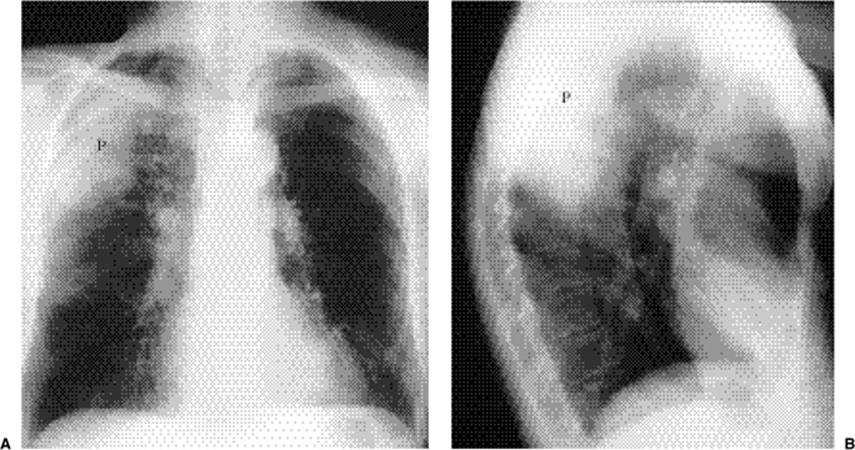

Focal opacity may be visible, especially when comparing one lung with the other on the frontal projection. On the lateral projection attention should be directed over the thoracic spine, the cardiac silhouette, and the retrosternal and retrocardiac regions, where faint opacity may otherwise escape detection (Figs. 5.1 and 5.2).

Figure 5.1 Opacity in pneumonia. (A) Posteroanterior and (B) lateral chest radiographs: minimal right basilar opacity, much better seen on the lateral view overlying the heart (P).

Figure 5.2 Opacity in pneumonia. (A) Posteroanterior and (B) lateral chest radiographs: vague retrocardiac abnormality (P) with corresponding increased opacity over the lower thoracic spine on the lateral view (arrows).